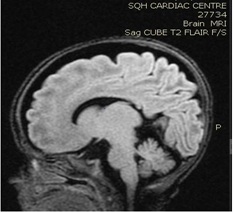

Brain MRI (images 1,2,3,4) at the age of 78 days; revealed that generalized relative simplified gyral pattern, generalized enlarged subarachnoid spaces as well as enlarged bilateral sylvian fissures, no diffusion restriction, no intracerebral hemorrhage, pituitary fossa appears normal in size, the posterior pituitary spot is not well defined.

Image 2

We were able to manage hypernatremia and polyuria with desmopressin and weaned the infant from a high fluid intake to a normal fluid intake per day [10-14]. The desmopressin response validated the diagnosis of central diabetes insipidus. Brain MRI data were also indicative of a central origin, particularly the posterior pituitary spot, which was not well delineated.  In comparison with previously reported cases, we controlled the case with a little dosage of oral desmopressin, and oral desmopressin is more practical than intranasal dDAVP treatment [15,16], and oral desmopressin administration and modification of dosage is easier than nasal application [17].